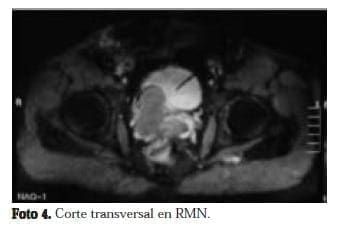

La resonancia muestra una masa multiloculada (foto 3 y 4) dependiente de la vesícula seminal derecha y agenesia renal ipsilateral. Se realizó además una ecografía transrectal de próstata, donde se identificó una gran masa quística que rechaza la pared posterior de la vejiga.

Con diagnóstico de quiste de vesícula seminal y agenesia renal ipsilateral, e l paciente se dejó en manejo expectante, teniendo en cuenta que estaba totalmente asintomático desde el punto de vista urológico.

La cistoscopia es útil si se detecta la ausencia del hemitrígono. La TAC da una muy buena imagen anatómica, pero la resonancia magnética es ideal por su habilidad para dar imágenes multiplanares. Usualmente los quistes dan una imagen de baja intensidad en T1 y alta en T2, aunque si hay hemorragia o un contenido protéico alto, puede dar una señal de alta intensidad en ambos.